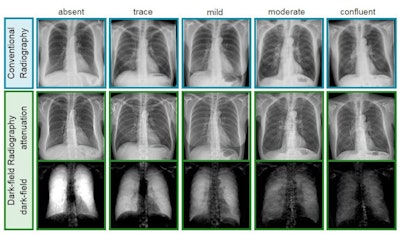

In this study, the group enrolled 88 patients with either no lung impairment or any stage of emphysema. CT scans served as a visual reference, with emphysema absent in 36 patients, trace disease in 21, mild in 11, moderate in nine, confluent in seven, and advanced in four patients.

Visual assessment of images was performed by clinical radiologists, with three readers categorizing conventional x-ray images and dark-field chest x-ray images as no emphysema, mild, moderate or severe.

Dark-field images showed a distinct decrease of signal strength with emphysema severity, as alveoli are denser in these patients, according to the findings. Readers were significantly better able to identify emphysema with images from the dark-field prototype, achieving an area under the curve (AUC) of 0.85 (p < 0.05) compared with conventional images (AUC, 0.74).

In addition, while ratings of adjacent emphysema severity groups with conventional radiographs were only different for trace and mild emphysema, ratings based on images from the dark-field prototype were different for trace and mild, mild and moderate, and moderate and confluent emphysema.

This was the first head-to-head study pitting the new technique against conventional chest x-rays, and more work is planned, Urban told AuntMinnie.com. The approach yields both attenuation and dark-field x-rays in a single acquisition, and these images may be combined, which could offer even more diagnostic accuracy, she added.